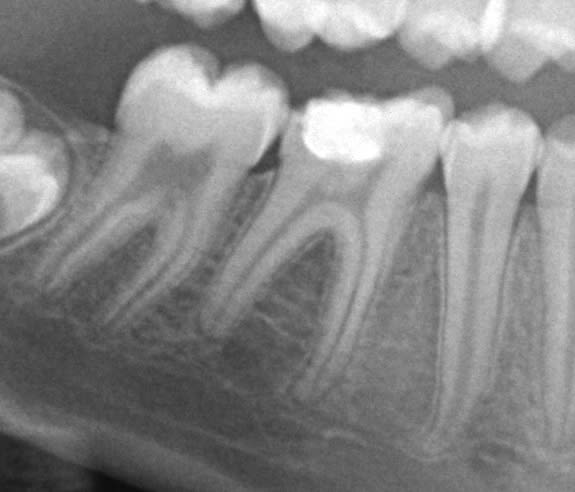

A 7 ans, cette demoiselle a eu une AG avec extractions de 14 dents temporaires.

A 10 ans, coca et chips à volonté, voici ses 11/21. Les 6 sont dans un état similaire.